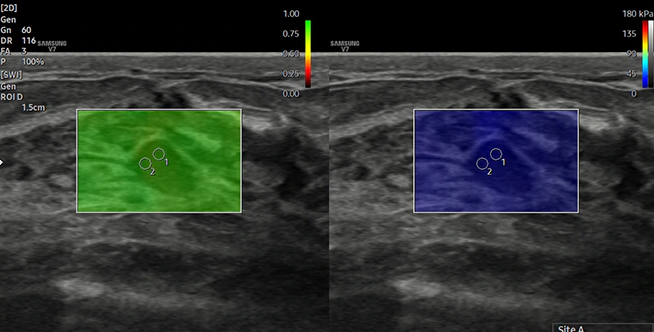

Elastografia fali poprzecznej S-Shearwave Imaging™, to dalszy krok w ocenie

tkanek miękkich, która pozwala wcześniej wykrywać zmiany chorobowe,

oceniać stopień ich zaawansowania.

Elastografia uciskowa ElastoScan+™ polega na zastosowaniu niewielkiego

ucisku na badany narząd. Wielkość odkształceń pod wpływem ucisku jest

przetwarzana i przedstawiana za pomocą kolorowych map, tzw. elastogramów.

Zmiany złośliwe zazwyczaj charakteryzują zmniejszoną sprężystością.

Odwrotnie dzieje się ze zmianami zapalnymi, które zazwyczaj posiadają

mniejszą sprężystość. Pozwala to na wczesne rozpoznanie zmian wymagających

dalszej diagnostyki, co ma to niezwykle istotne znaczenie we wczesnym

rozpoznawaniu groźnych chorób.